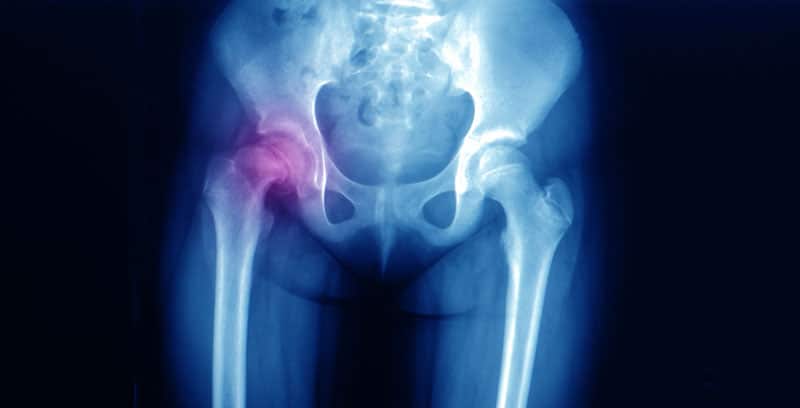

X-ray of an adolescent male patient showing slipped capital femoral epiphysis (dislocation) on right hip.

Hip Injuries

Common car accident-related hip injuries include fractures to the hip bone or hip socket, inflammation of the bursae, hip dislocation, and tendonitis.  While some injuries may heal quickly and completely, others can cause long-term complications including traumatic arthritis.